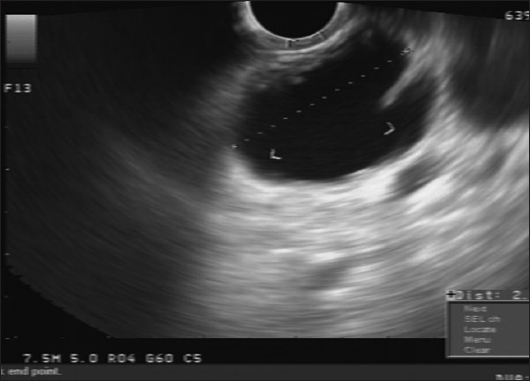

EUS has evolved as a therapeutic modality in the diagnosis and management of pancreatic diseases. EUS-guided ablation of pancreatic cysts provides a potentially less invasive treatment option in appropriately selected patients, with less morbidity and mortality compared with surgery [5] (Fig. 3). Additionally, pancreatic cyst ablation, if successful, could potentially lengthen surveillance intervals or reduce the need for periodic surveillance. EUS-guided approaches enable real-time imaging of the pancreatic lesions and would allow endoscopists to approach less accessible cystic lesions.

thumblarge

Figure 3 Endoscopic ultrasound fine-needle aspiration needle in a septated mucinous cystic neoplasm of the pancreas. The needle could be used to both aspirate the cyst contents and inject an ablative agent